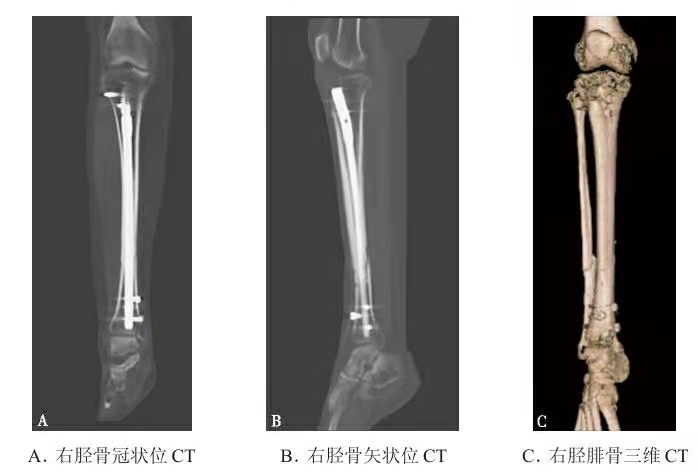

右 脛骨 骨折- 診断結果は「右脛骨・腓骨骨折」。 つまり、右足の膝から下の二本の骨が折れてるわけです。 「脛骨(けいこつ)」は太い方の骨、下の方の付け根部分辺りを骨折。 「腓骨(ひこつ)」は細い方の骨、二ヶ所折れて三つに分断されてました。 その脛骨の関節面にくっついています。 これは1つ特徴ですね。 前十字靱帯付着部剥離骨折の症状は?型の右脛骨外顆骨折を受傷した(図8)。 受傷8日目に骨移植を加えた骨接合術を 施行した。術後3週で1/3部分荷重歩行 を開始,術後4週で退院した。

胫骨开放性骨折髓内针固定 骨科与显微外科专业讨论版 爱爱医医学论坛